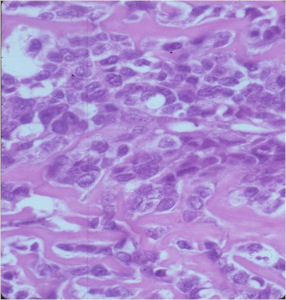

Aggressive Osteoblastoma

- Aggressive osteoblastoma is a distinct rare type of osteoblastoma that has a much more aggressive local behavior than a conventional osteoblastoma. They have a higher chance for local recurrence after removal.

- There has been controversy about the true existence of this type of tumor and whether these tumors are actually low grade osteosarcomas.

- They have a similar appearance microscopically as a conventional osteoblastoma except the osteoblasts are twice as large and have an epithelioid quality with abundant eosinophilic cytoplasm (Epithelioid Osteoblasts).

- Aggressive osteoblastoma is a borderline lesion lesion between osteoblastoma and osteosarcoma. It is not a precursor to osteosarcoma. It does not metastasize.

The differential between osteoid osteoma, conventional osteoblastoma and aggressive osteoblastoma is based on size and the presence of epithelioid osteoblasts. Can have epithelioid osteoblasts in osteoid osteoma and conventional osteoblastoma but they do not occur in cohesive sheets that fill intertrabecular spaces

Aggressive Osteoblastoma vs. Osteosarcoma

Osteosarcoma:

- Cellular atypia

- High mitotic rate

- Atypical mitotic figures

- Abundant lacelike osteoid

- Permeative growth into adjacent bone and soft tissue

- Presence of neoplastic cartilage

- No peripheral shell of reactive bone